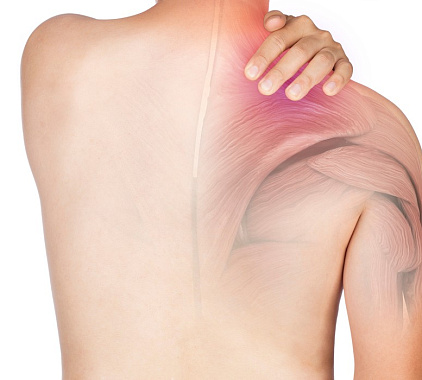

Показания к рентгену лопатки

Ситуации, когда требуется рентген лопатки:

- постоянная или временная боль, дискомфорт в лопатке неясного происхождения;

- болезненность в плечевом суставе;

- отек тканей лопатки, видимая гиперемия;